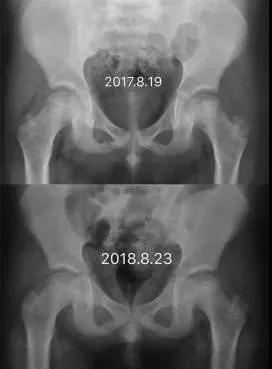

Perthes病即儿童股骨头特发性缺血性骨软骨病,于1910年被Legg、Calve、和Perthes三位学者总结报道,因此也称为Legg-Calve-Perthes病,简称LCPD。发病早期,患儿往往出现跛行和患侧大腿中下段的疼痛不适、有时甚至是健侧膝盖周围疼痛,休息几天就可以缓解。但由于儿童天性活泼好动,上述症状常常容易复发。因此好多孩子常常被家长乃至初诊医生忽视、只是简单认为是“滑膜炎”、“缺钙”或者所谓“生长痛”,没有早期发现并且及时确诊、科学施治,而遗留了头臼曲率适应不佳、髋臼覆盖不良、股骨近端形态异常等等生长发育畸形(图1),导致髋关节出现软骨磨损继而早发骨性关节炎,从而严重影响日常生活和工作。而如果能够早发现早治疗,LCPD完全可以获得优良结果乃至正常髋关节状态(图2)!

图2 LCPD患者影像学变化